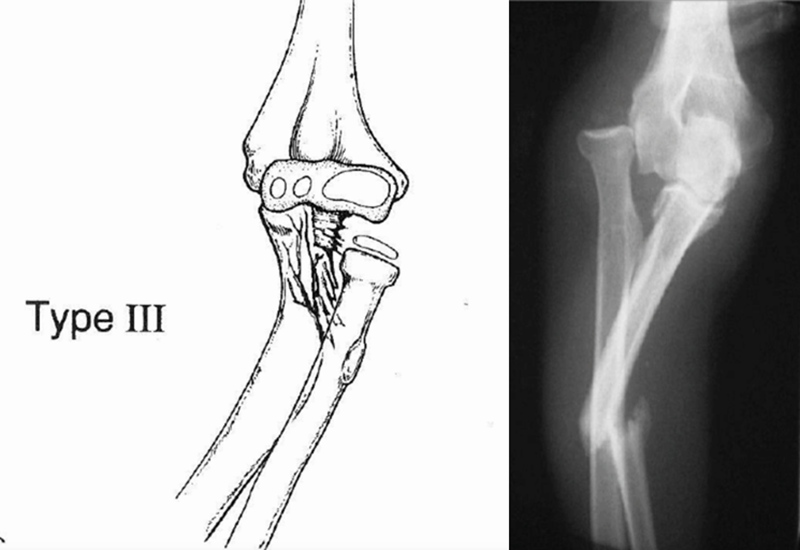

目前临床上主要采用Bado分型方法,即根据尺骨骨折和桡骨小头脱位的方向,分为Ⅰ、Ⅱ、Ⅲ、Ⅳ四型。

Ⅲ型(内收型):桡骨头后外侧或是前外侧脱位,尺骨近端骨折且可累及干骺端,仅在儿童中发病,又称为儿童型,约占7%~20%。

受伤机制:在肘关节内翻应力的作用下,先造成尺骨近端的青枝骨折,使桡骨头向外侧或前外侧脱出。